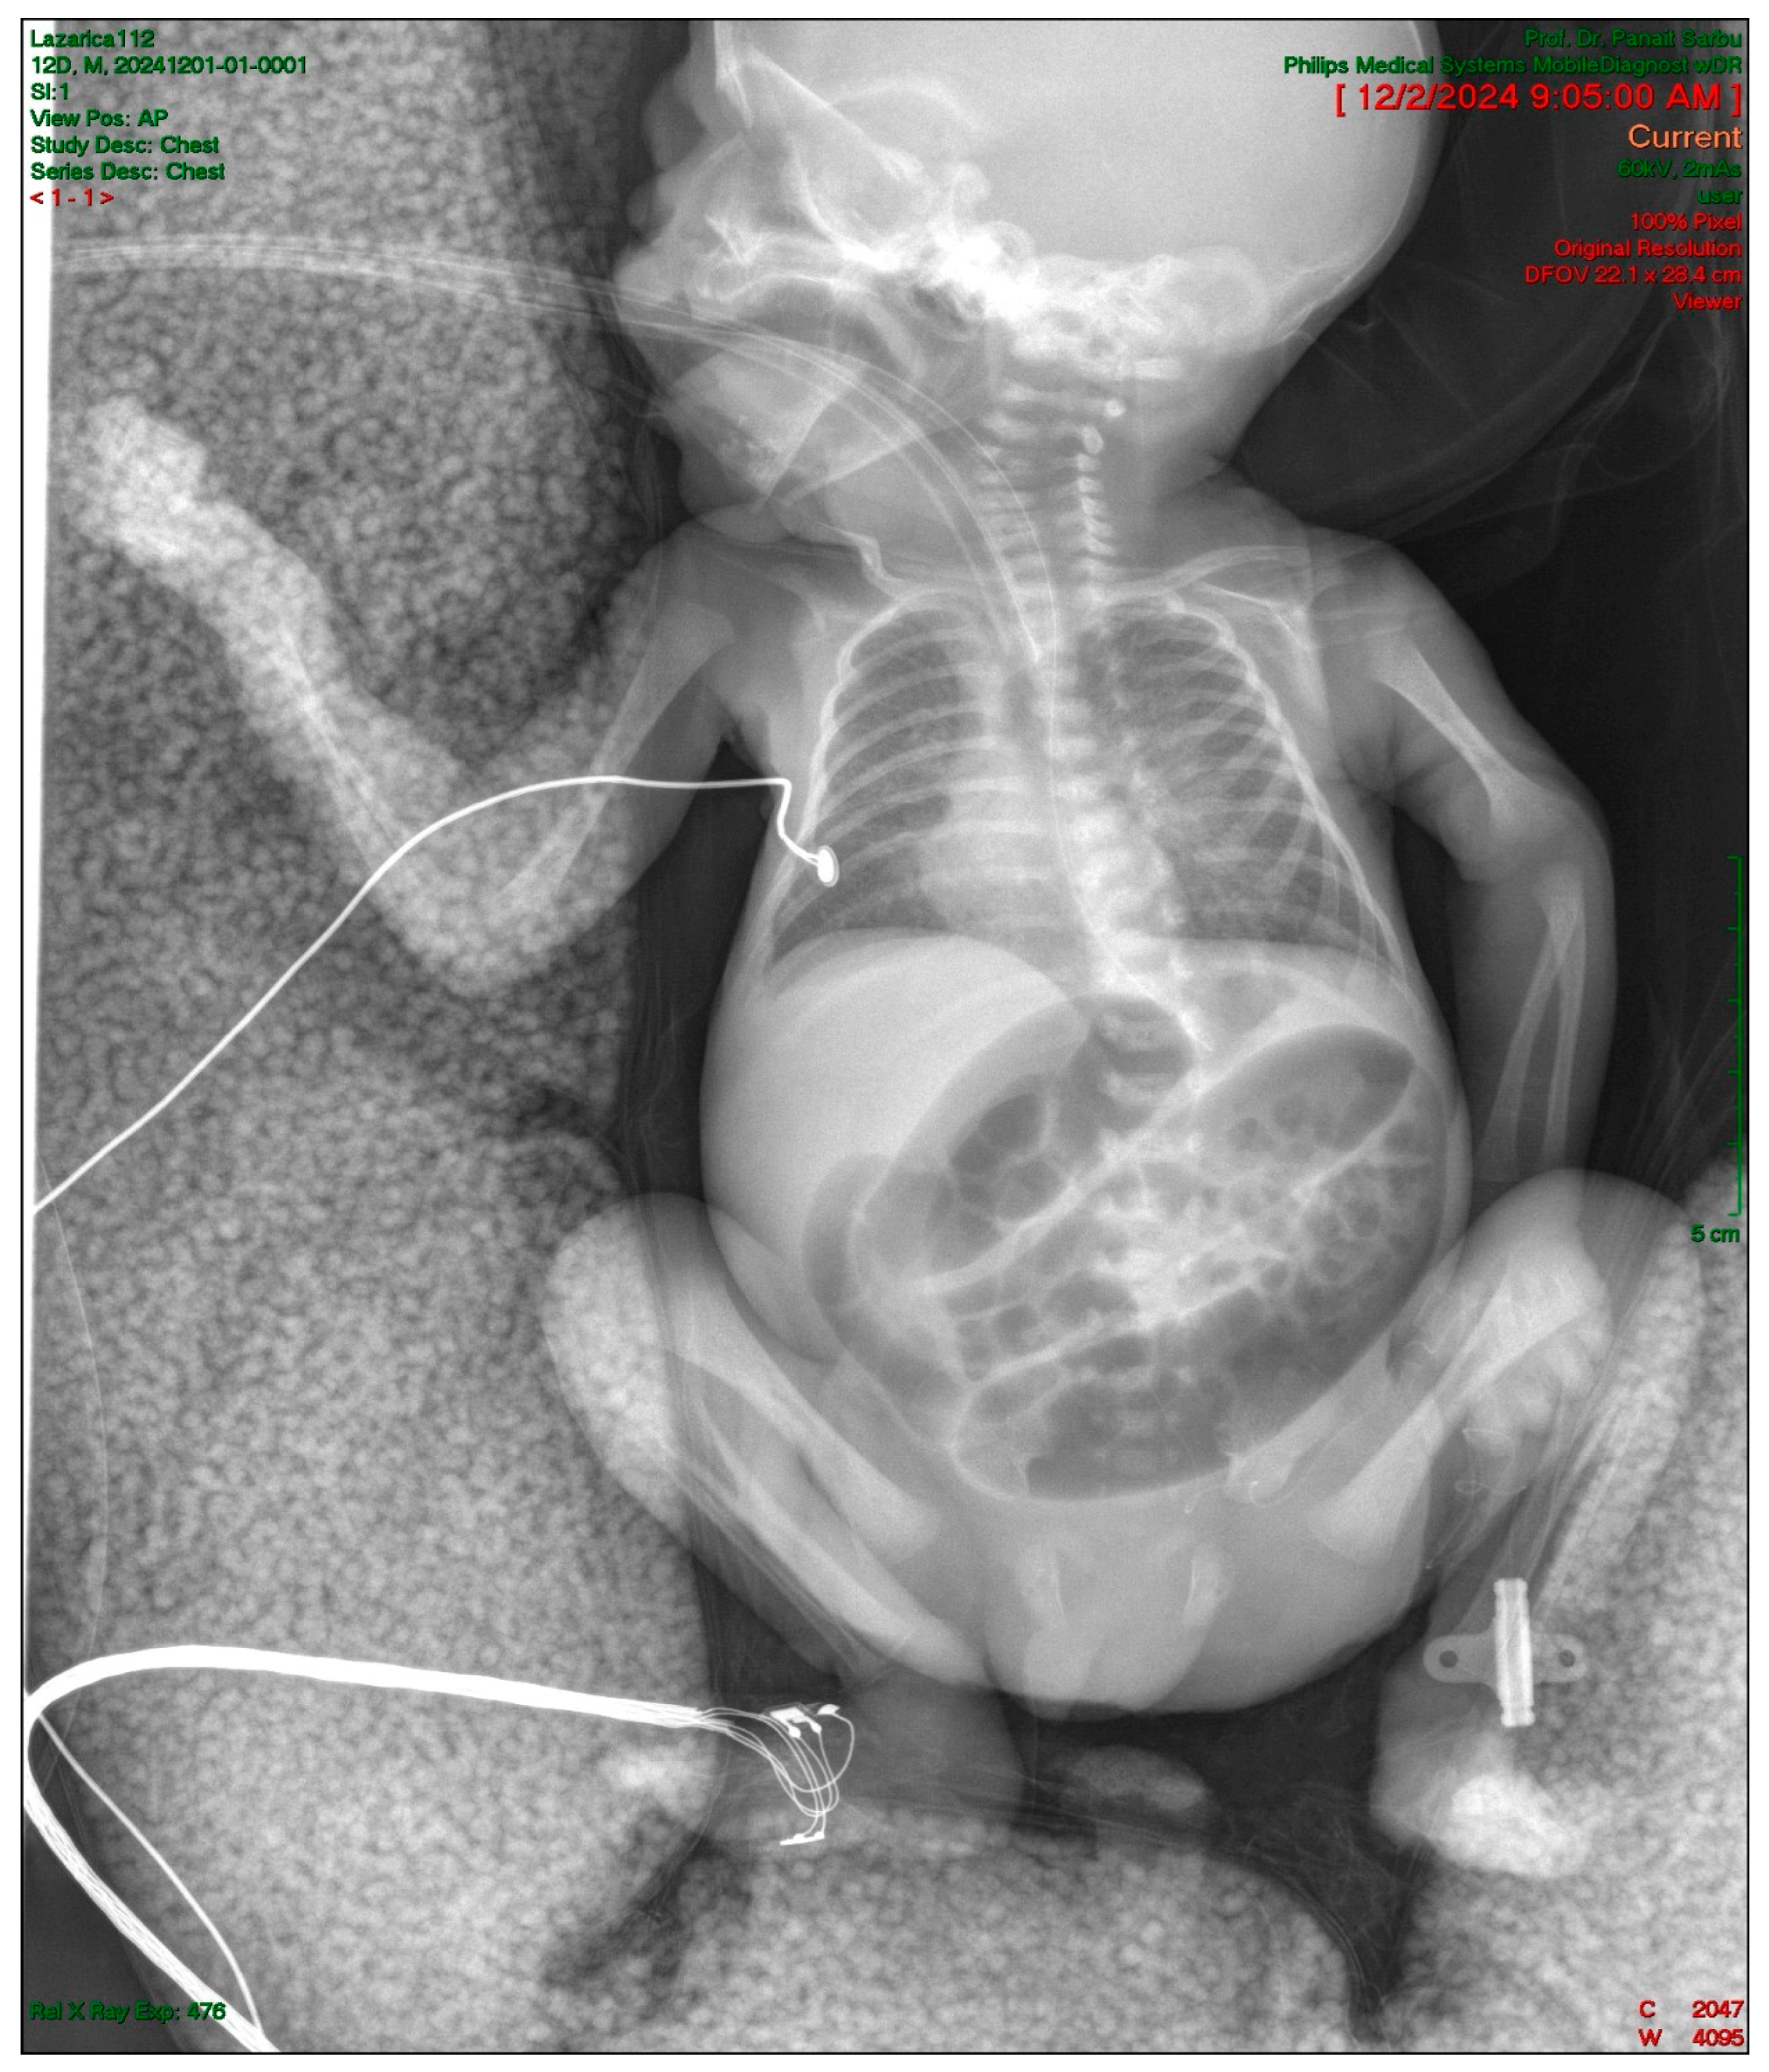

2.4. Gastrointestinal Complications and Diagnosis

| Day 12 | Intestinal obstruction suspected | Surgical consultation |